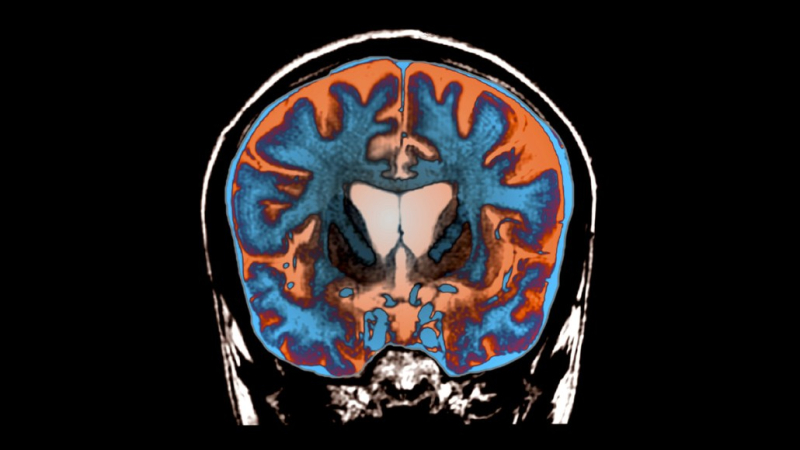

Это мозг человека с болезнью Хантингтона. Желудочки — открытые полости для циркуляции спинномозговой жидкости — расположены в центре и намного больше, чем обычно, что является признаком дегенерации близлежащих областей мозга.